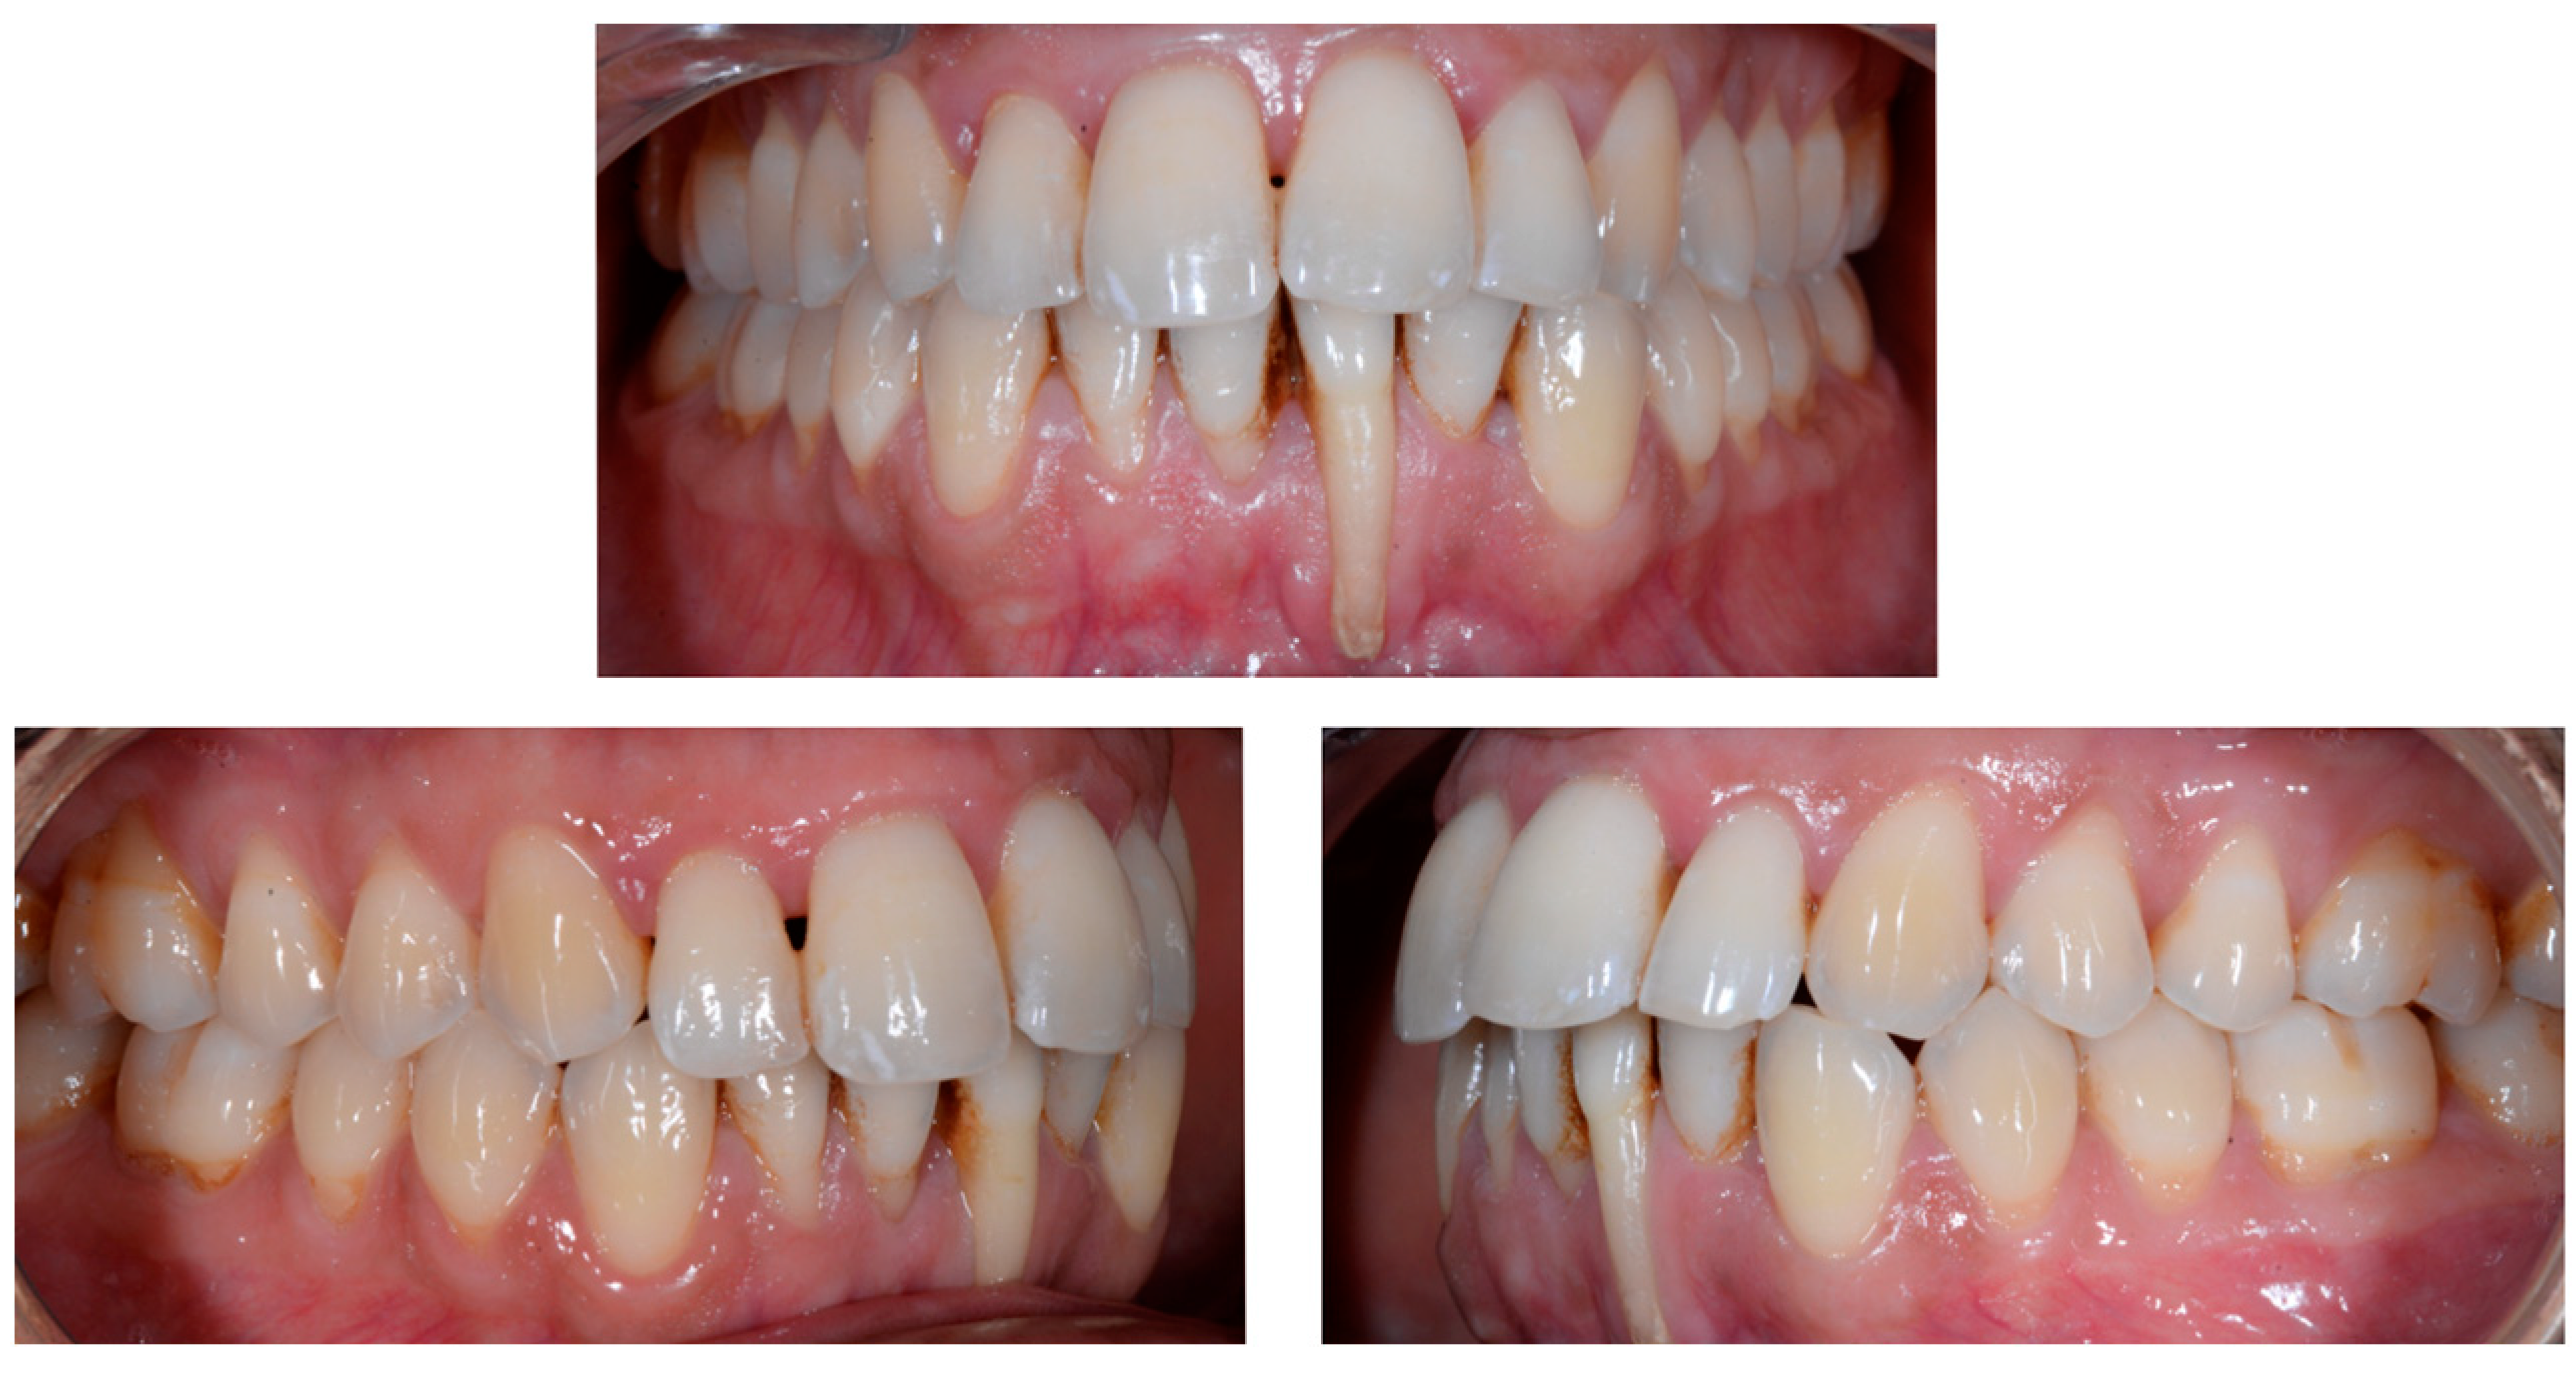

A 26-year-old female patient was referred by her general dentist for suspected wire syndrome. Orthodontic treatment had been performed 10 years previously, and bonded restorations had been fitted at the end of the treatment. The patient mentioned several episodes of breakage/adhesion, without further details. She has good oral hygiene and a right and left Class I (Figure 5).

Figure 5.

Intermediate wire syndrome. Frontal and lateral views.

In Figure 6, 11 and 21 show a difference in incisal edge height and gingival margin. Tooth 41 shows gingival recession to the muco-gingival junction (Cairo’s RT1) with root visibility. Tooth 33 had a significant lingual tilt (coronal–lingual torque), not symmetrical to tooth 43.

Figure 6.

Intermediate wire syndrome. Frontal view.

The root of tooth 21 is visible through the gingiva (Figure 7). Figure 8 shows the extent of gingival recession on tooth 41.

Figure 7.

Intermediate wire syndrome. Lateral view.

Figure 8.

Intermediate wire syndrome. Lateral views.

The occlusal views provide additional relevant information (Figure 9 and Figure 10). A maxillary retainer was present on 11 and 21 only and a difference in visibility of the vestibular surfaces (differential torque) on these same teeth was noted.

In the mandible, the retainer was broken distal to 42 and, despite being intact on 33, this tooth had increased visibility of its vestibular surface compared to its contralateral tooth (differential torque). Finally, teeth 31 and 41 also showed a difference in the visibility of their vestibular surfaces (differential torque). Ultimately, the patient was diagnosed with an X-effect wire syndrome on 21, an X-effect wire syndrome on 41, and a Twist-effect wire syndrome on 33.